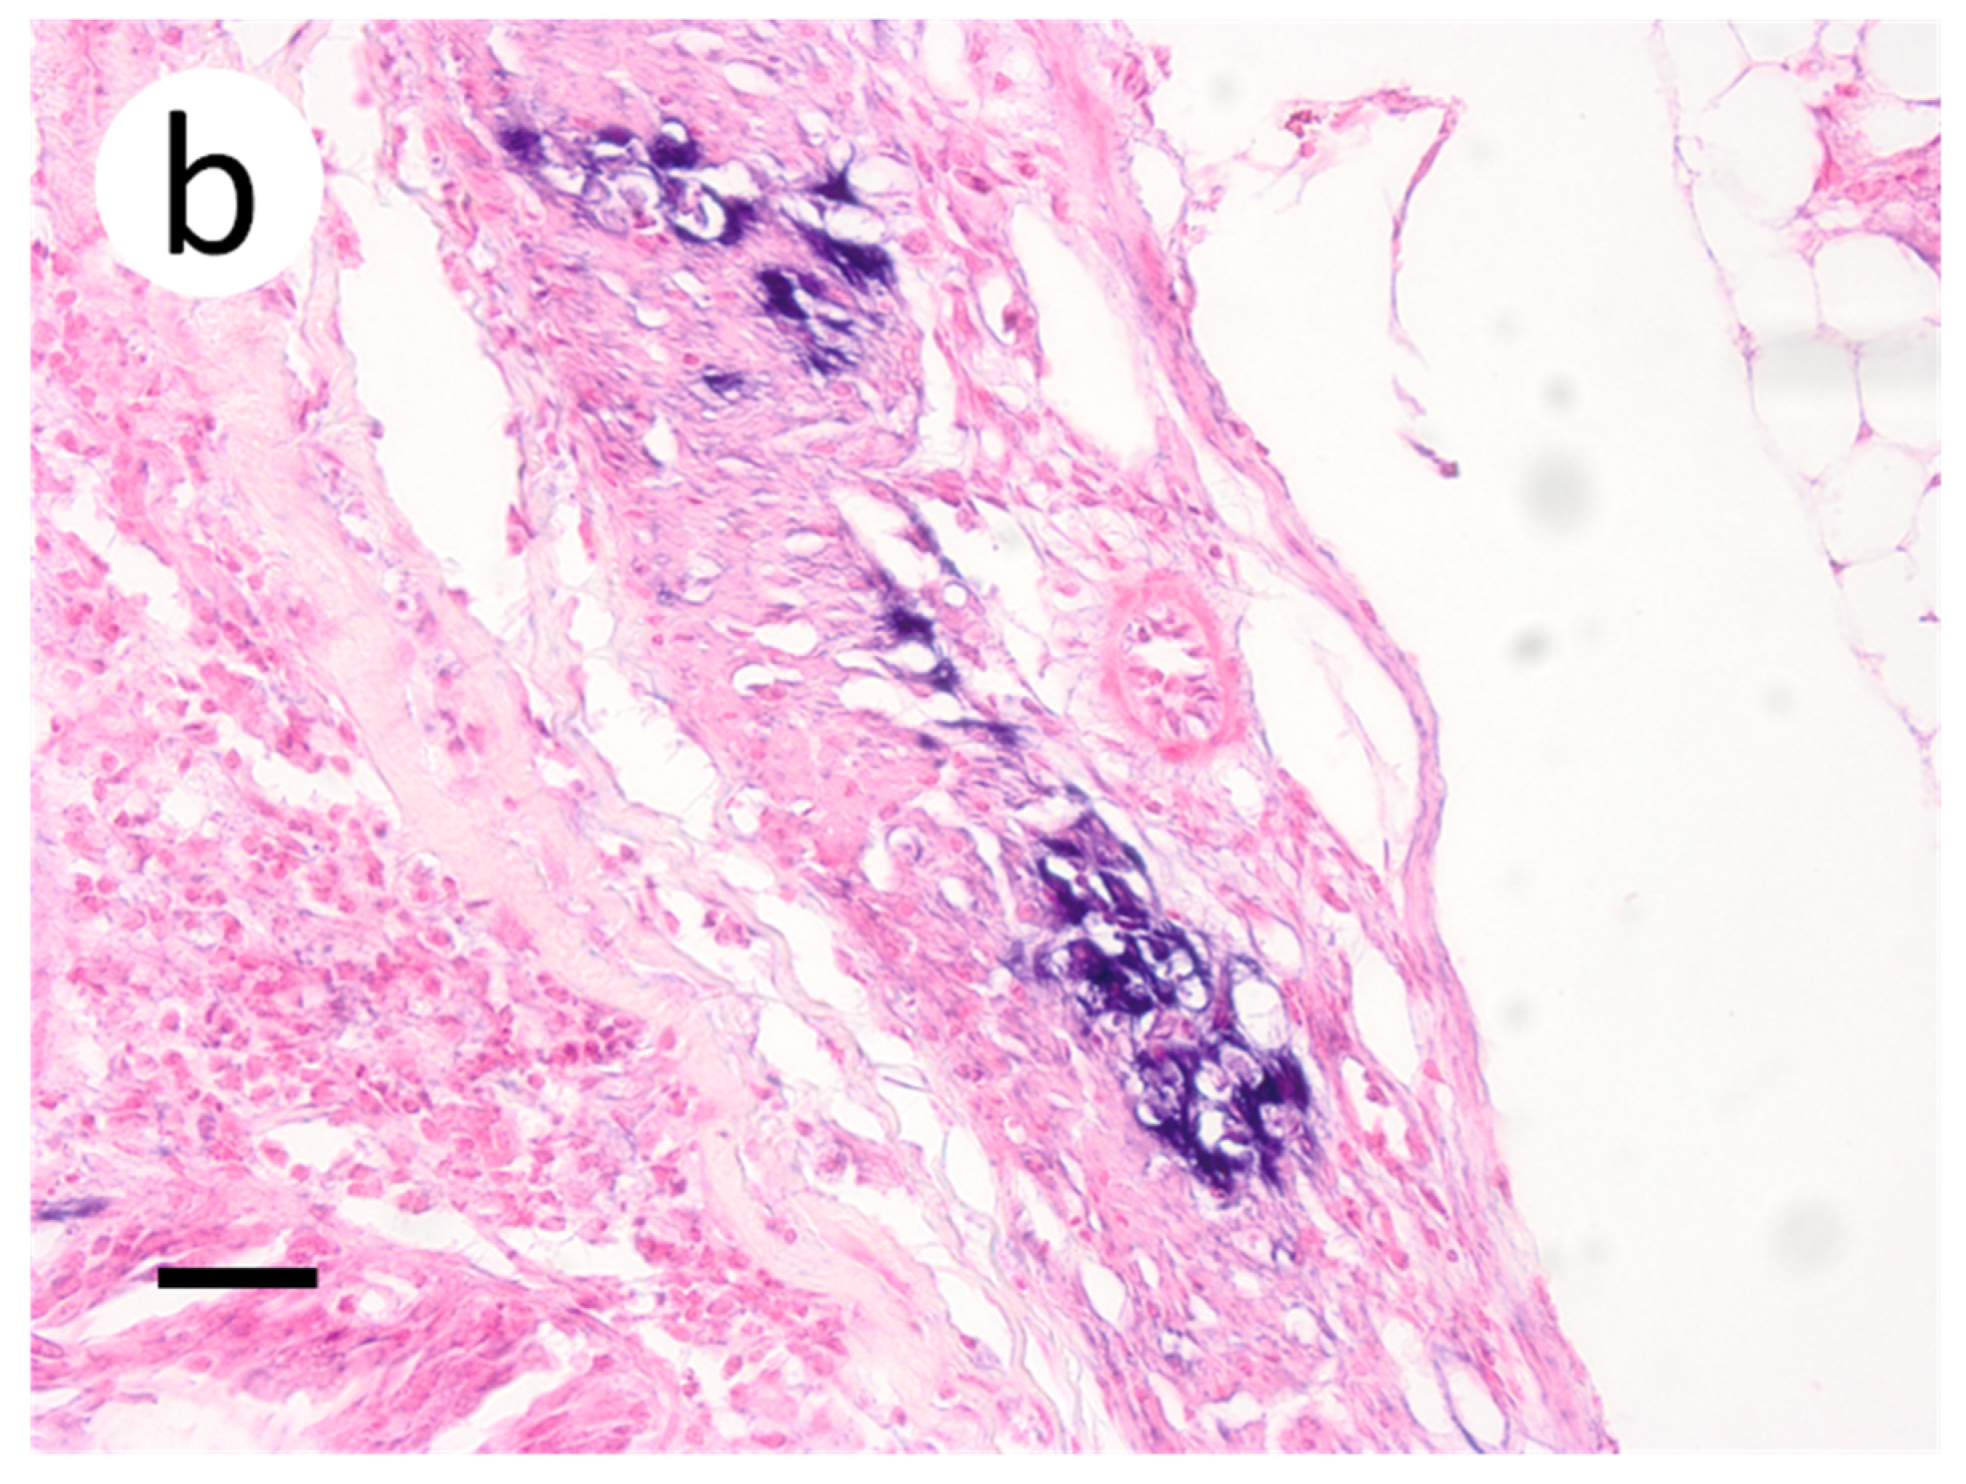

3.3. Visualization of VHSV-IVb in Tissues of Infected Muskellunge